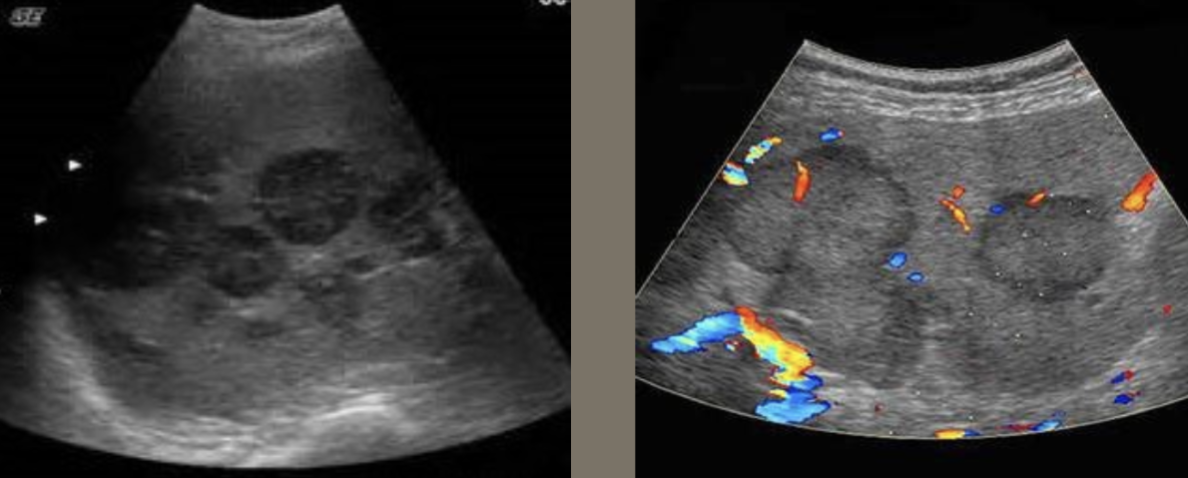

Lymphoma → lymphocyte proliferation in lymph nodes

2D US: multiple hypoechoic masses, lobular, poor margins, encases vasculature, periportal enlarged hypoechoic lymph nodes, splenomegaly

color doppler:

DDX: METS, HCC